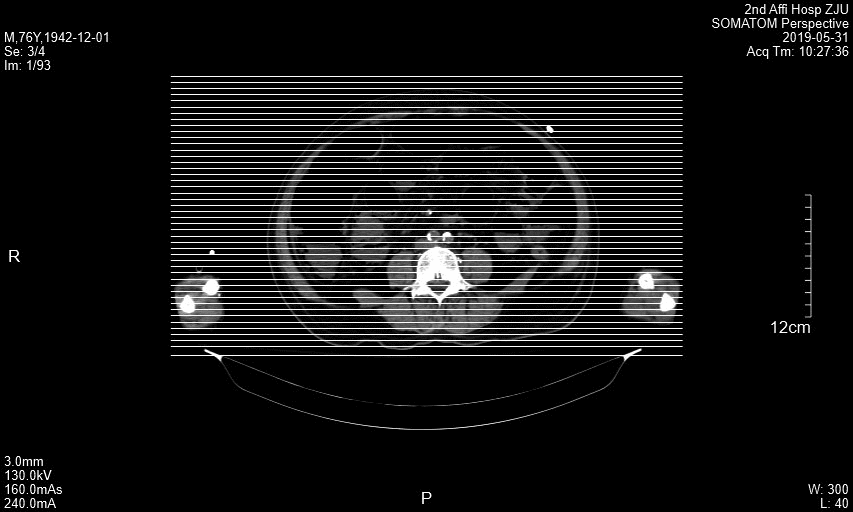

王瑞林_正位片.jpg